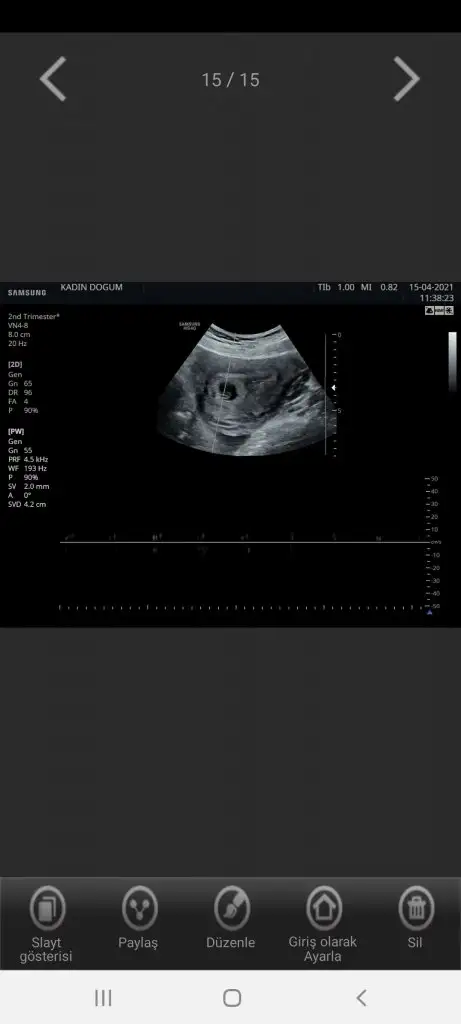

Banada yorum yaparmısınız 7+1 alttan muane ile bakıldı kalp atıslarını duydumuz gün. Hiç farketmiyor cinsiyeti ama ramzi diye bişey duydum 🤗